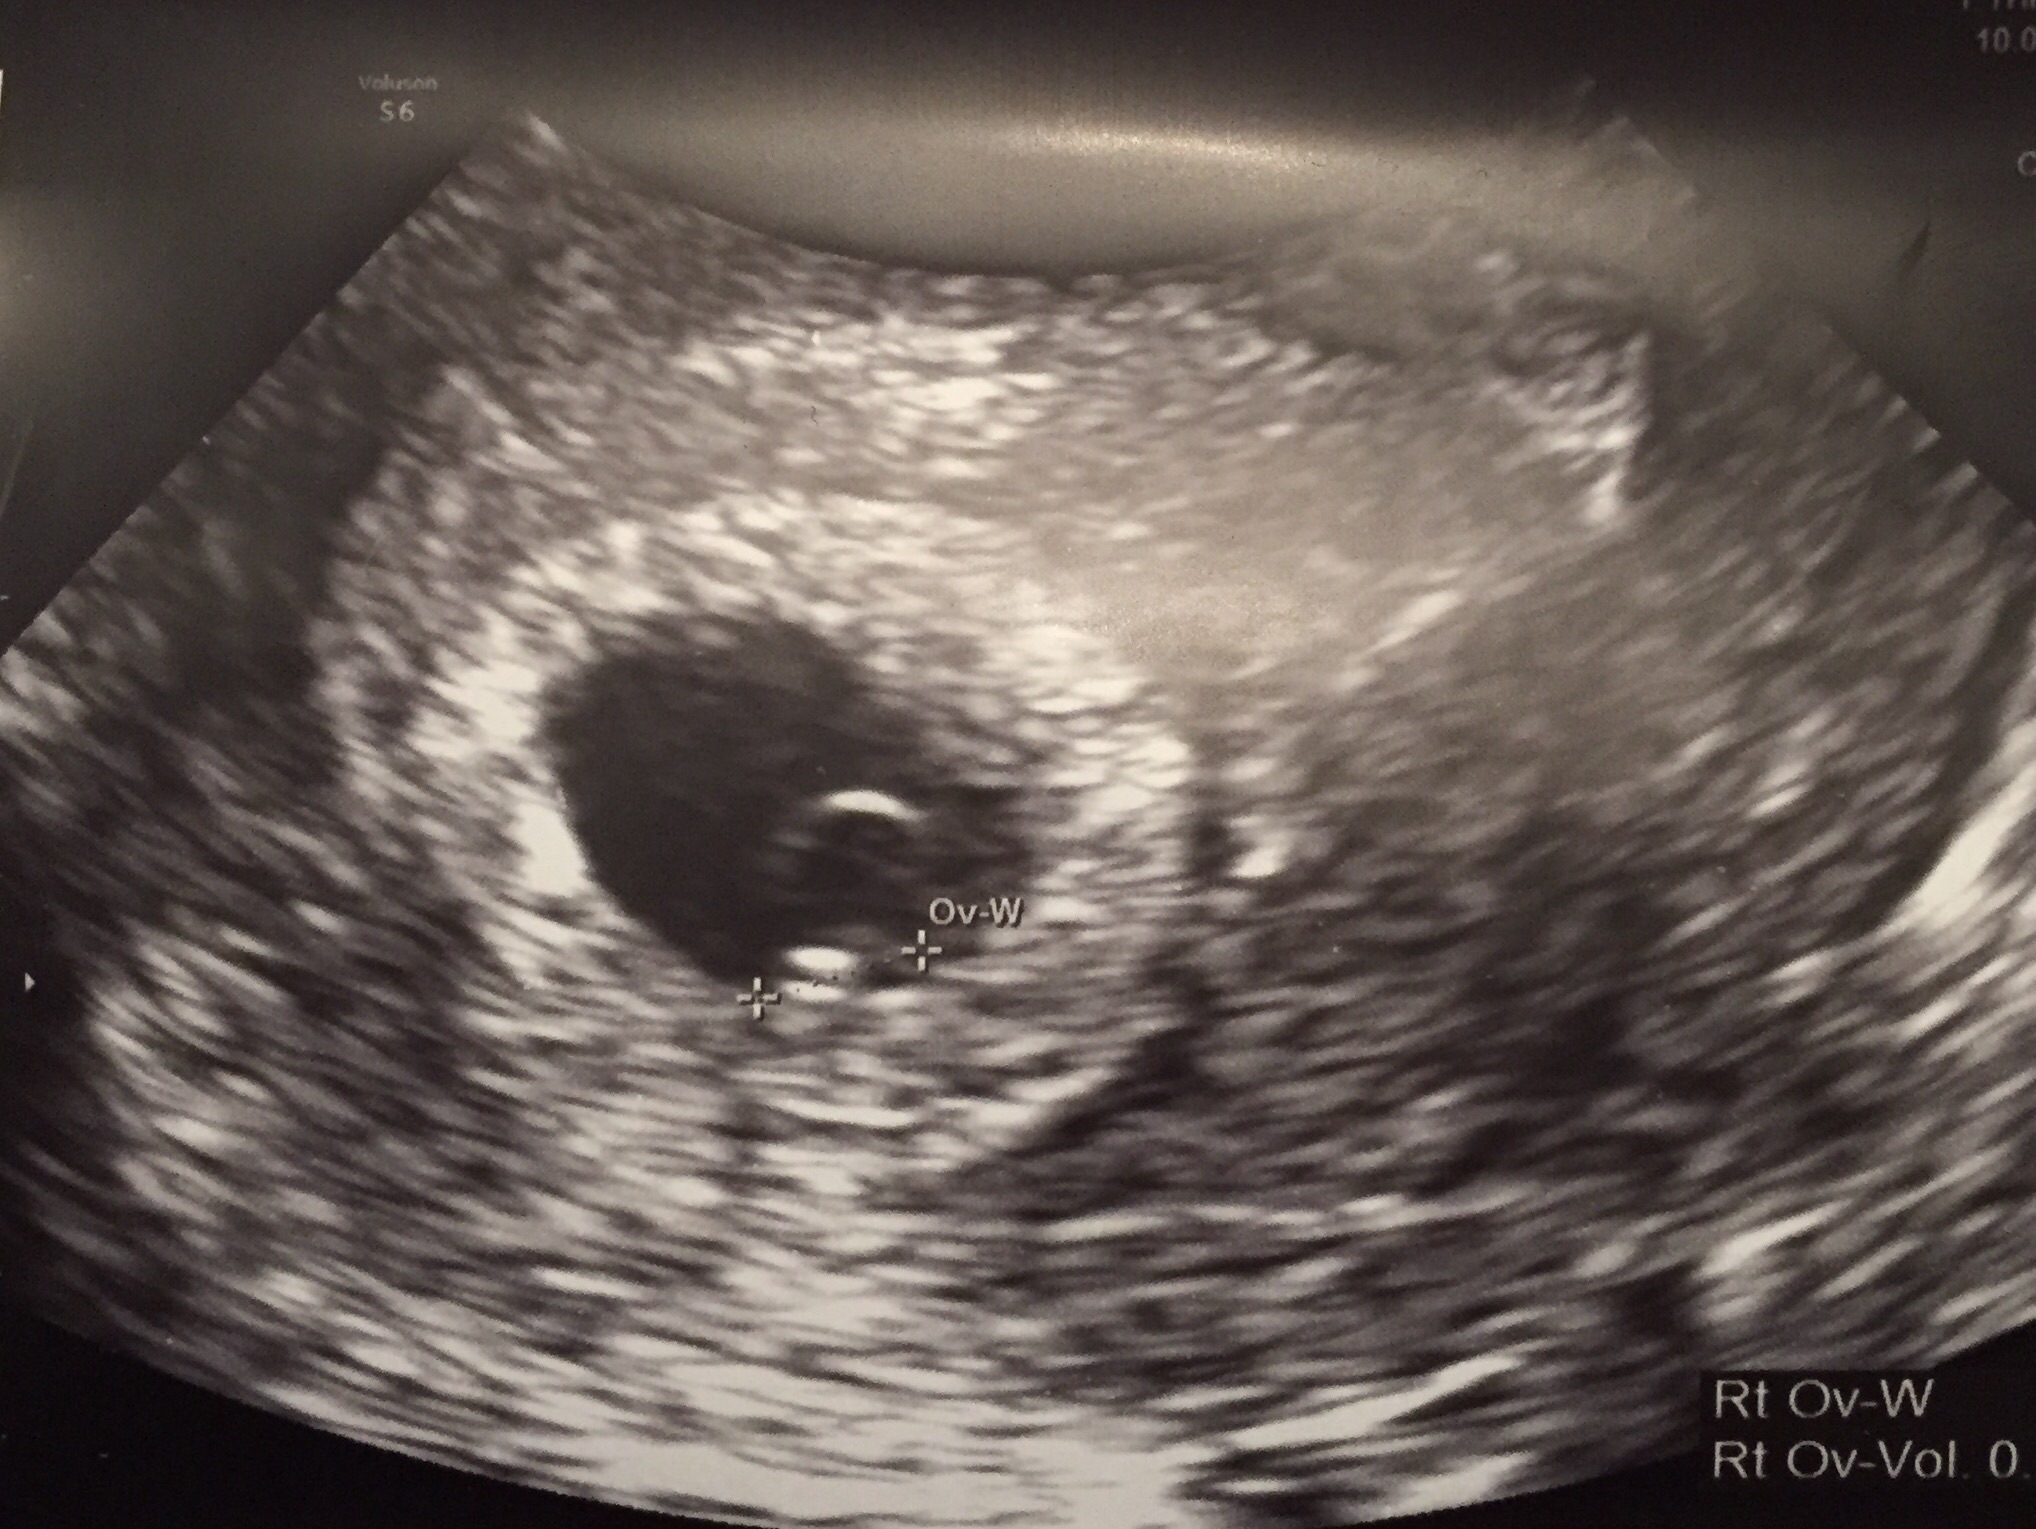

• I did! The earliest they'd let me come in was 6w6d...according to my LMP I am 7w2d today, but after my ultrasound they measured me at 6w6d, but let me keep my due date of 10/24.

Felt so incredibly relieved to see the flutter of a little heartbeat (125bmp)...PCOS, 5 years of infertility and no symptoms had me super nervous.

Good luck & hang in there!

Attatched a pic from today :)